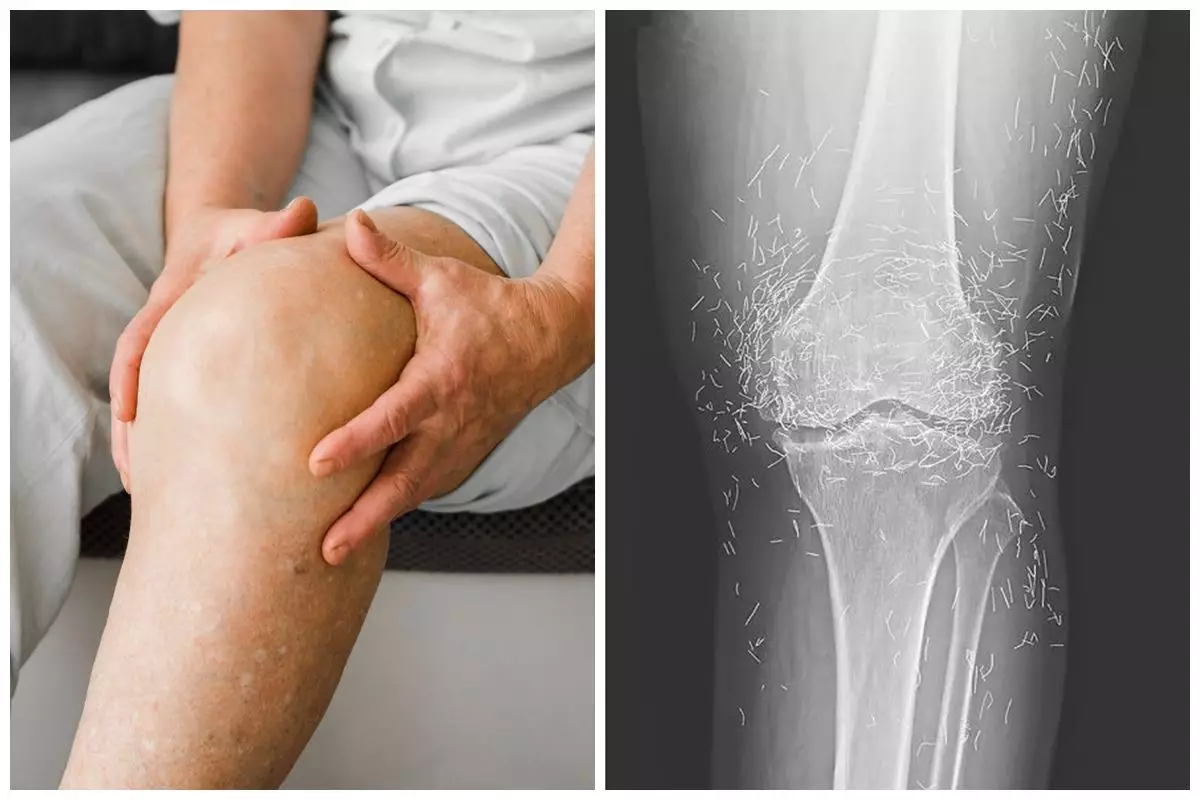

Pihak medis menjelaskan pasien awalnya datang ke rumah sakit dengan keluhan lutut yang terasa sangat nyeri. Setelah dilakukan pemeriksaan lebih lanjut, hasil rontgen menunjukkan adanya perubahan bentuk pada tulang kering bagian dalam lutut yang tampak menebal dan mengeras.

foto: The New England Journal of Medicine

Selain itu, pertumbuhan tulang kecil atau bone spurs juga muncul di sekitar sendi lutut. Pada saat yang sama, dokter melihat adanya bintik-bintik putih dalam jumlah besar yang ternyata merupakan benang emas.

Temuan itu kemudian diidentifikasi sebagai bagian dari prosedur akupunktur dengan teknik khusus. Benang emas steril tersebut sengaja ditanamkan di jaringan tubuh pasien untuk memberikan stimulasi jangka panjang.

"Ia kemudian datang ke rumah sakit karena lututnya sangat nyeri. Rontgen pada lutut kirinya menunjukkan tulang kering bagian dalam menebal dan mengeras. Ada juga pertumbuhan tulang kecil di sekitar tulang kering dan tulang paha dekat sendi lutut," imbuhnya.

Temuan mencengangkan muncul dalam hasil rontgen berikutnya. Ratusan benang emas terlihat jelas menempel di sekitar sendi lutut.

"Dokter juga melihat ratusan bintik putih pada hasil rontgen di sekitar sendi lutut, yang ternyata adalah benang emas kecil," ungkapnya.